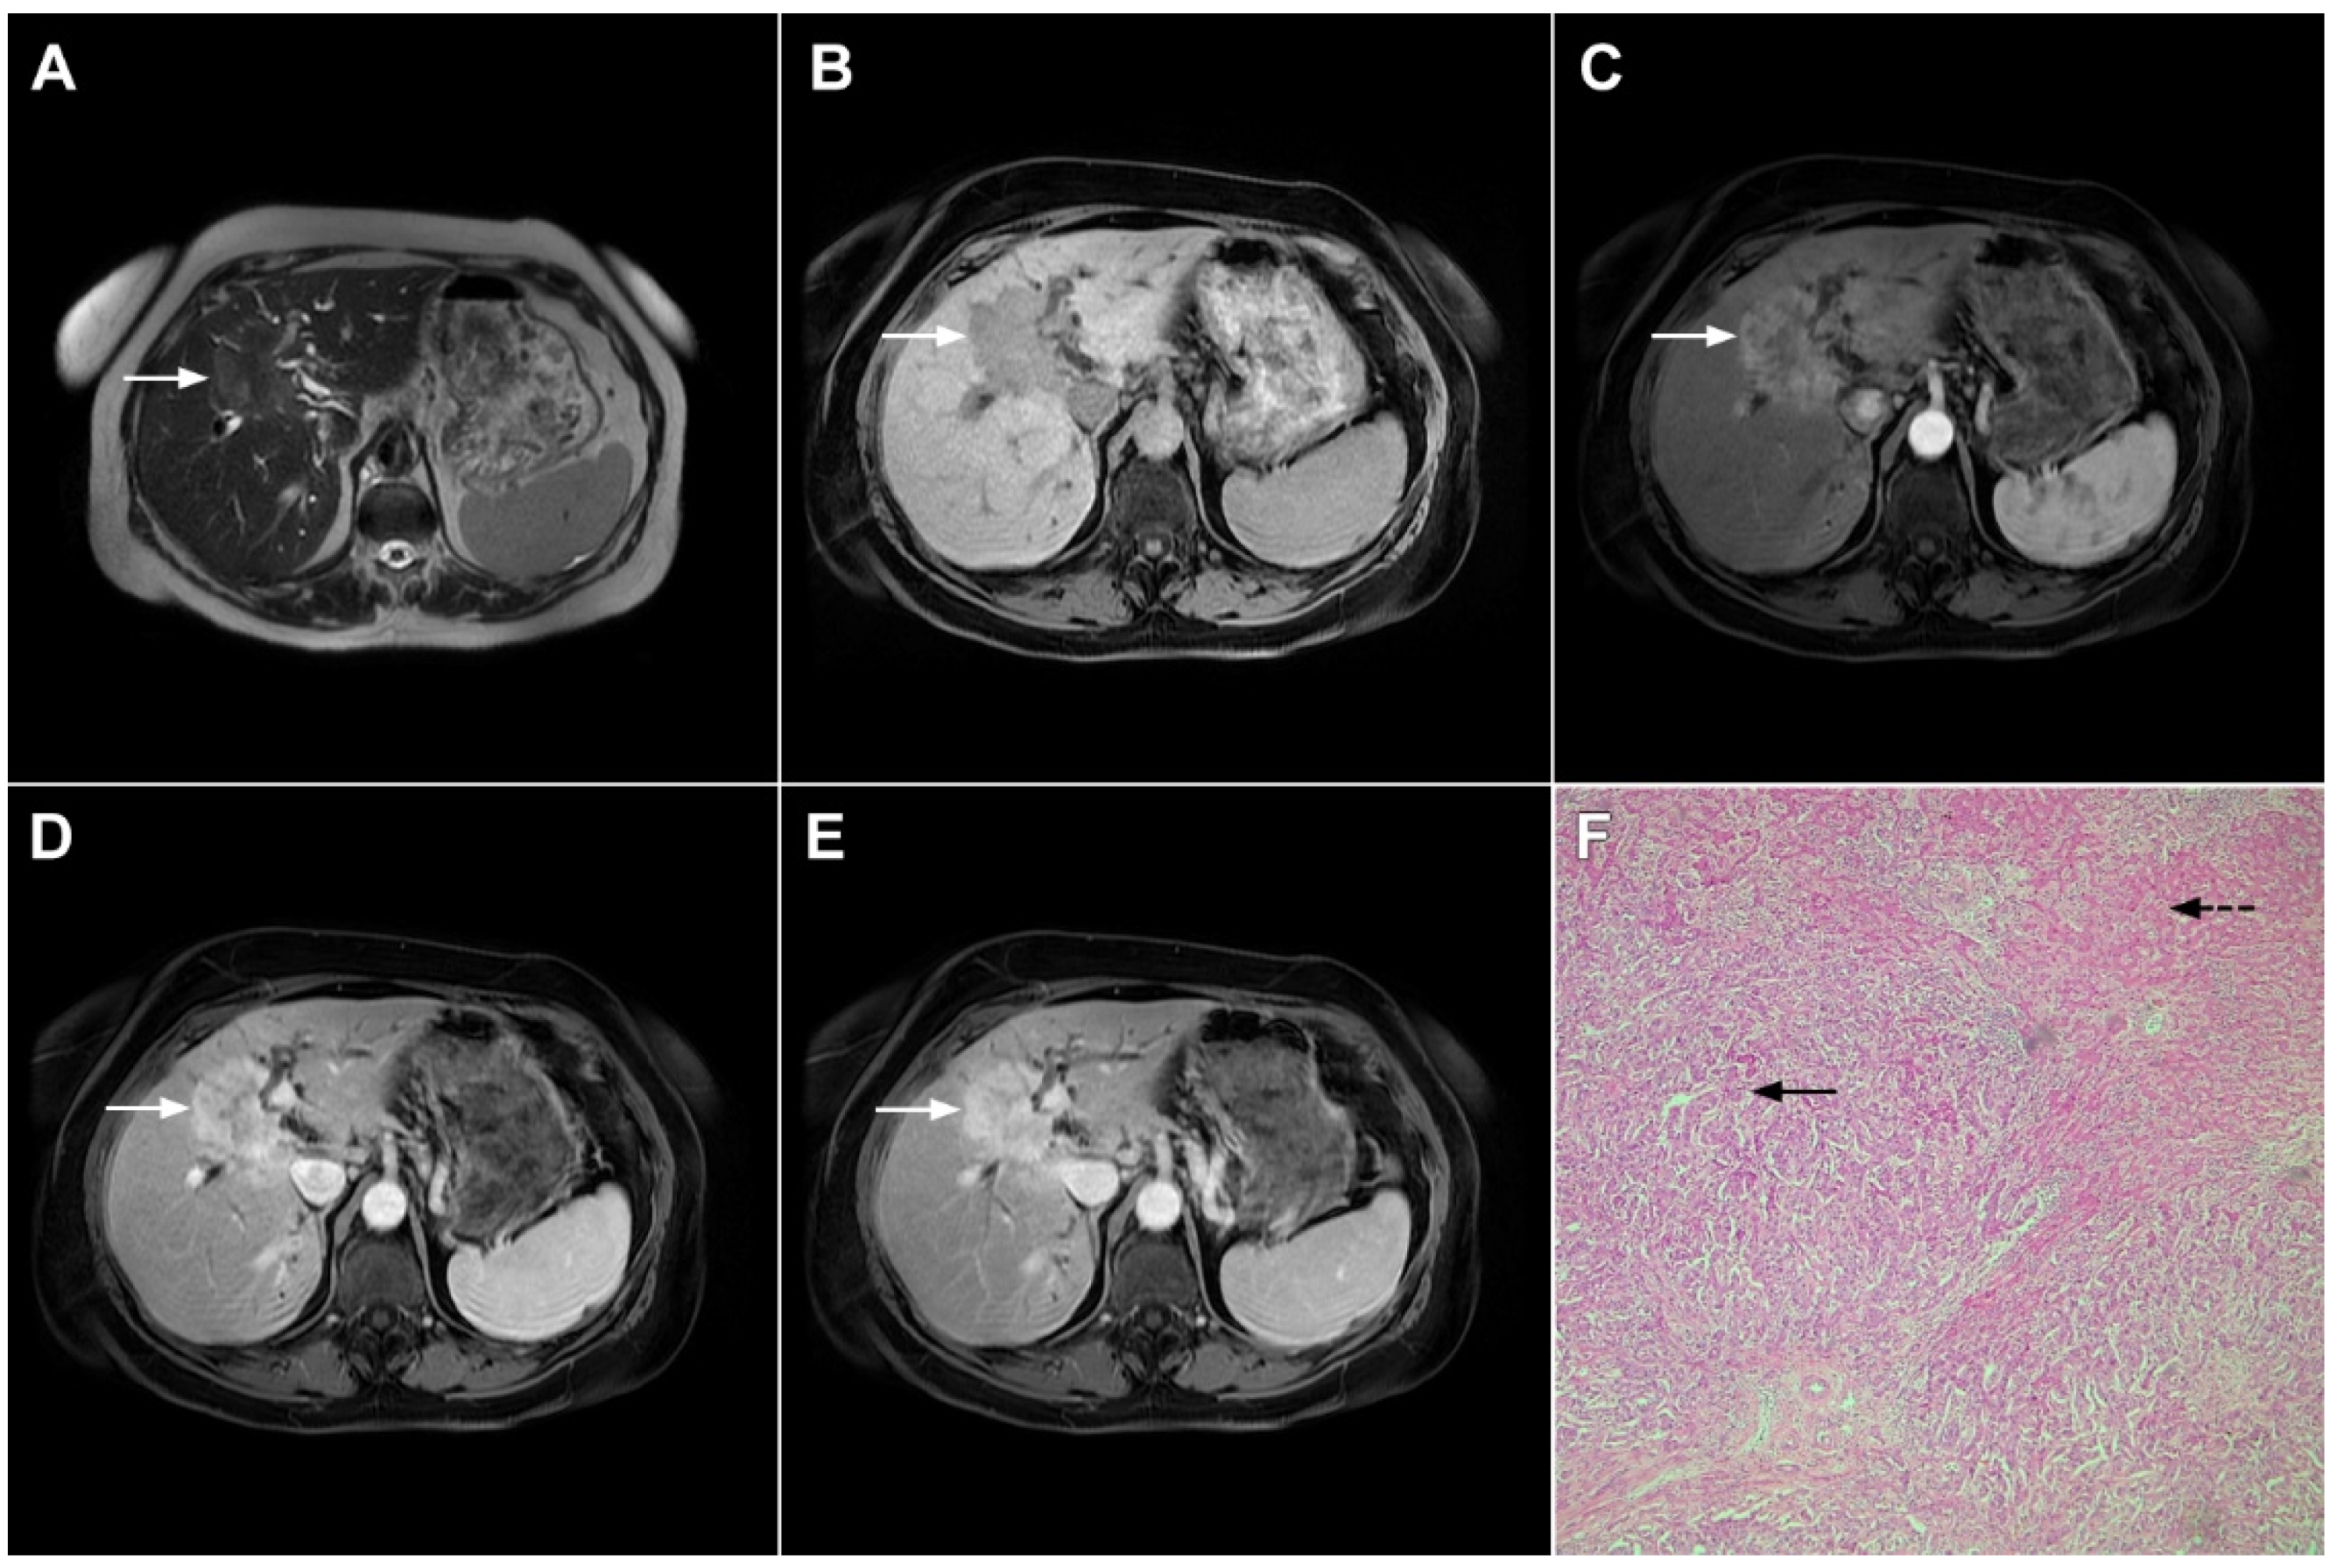

2.1. Typical Imaging Features of mICC

2.2. Atypical Imaging Features of mICC